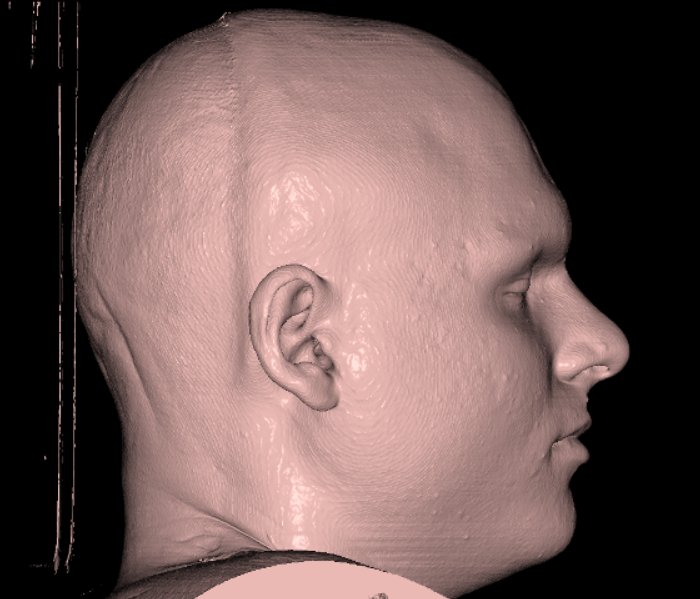

Here is how my side profile looks IRL:

Here is how my side profile looks IRL: